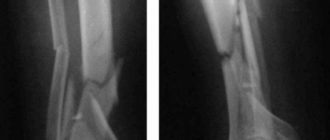

Деформация большеберцовой кости

Остеохондропатия бугристости большеберцовой кости Большинство заболеваний опорно-двигательной системы, связанных с изменением структуры и плотности